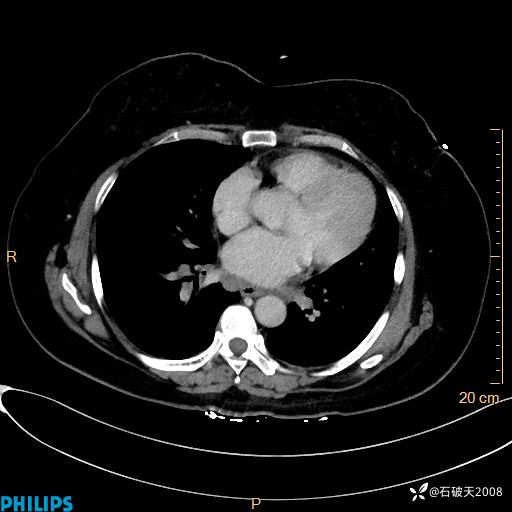

动脉期